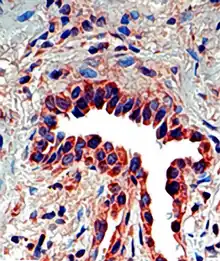

Tissue distribution

Osteopontin is expressed in a variety of tissue types including cardiac fibroblasts,[25] preosteoblasts, osteoblasts, osteocytes, odontoblasts, some bone marrow cells, hypertrophic chondrocytes, dendritic cells, macrophages,[26] smooth muscle,[27] skeletal muscle myoblasts,[28] endothelial cells, and extraosseous (non-bone) cells in the inner ear, brain, kidney, deciduum, and placenta. Synthesis of osteopontin is stimulated by calcitriol (1,25-dihydroxy-vitamin D3).